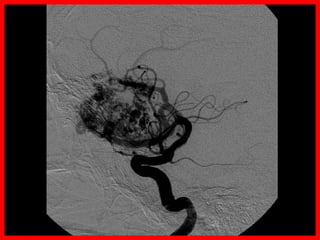

ACVh M - MAV

• Las malformaciones arteriovenosas están

formadas por un ovillo de vasos dilatados que

forman una comunicación anormal entre el

sistema arterial y venoso, constituyendo una

fístula areriovenosa.

• Se trata de una anormalidad del desarrollo

caracterizada por la persistencia de un patrón

embrionario de vasos sanguíneos.

ACVh M - Diagnóstico

ACVh M - Tratamiento

• Depende de factores dependientes del riesgo

vital del sujeto y de factores relacionados con la

morfología, localización y tamaño de las

malformaciones.

• La escala de Spetzler ayuda a valorar el riesgo

de la cirugía.

• Según la valoración global se pueden utilizar los

siguientes abordajes de forma aislada o en

combinación.

– Cirugía

– Embolización

– Radiocirugía